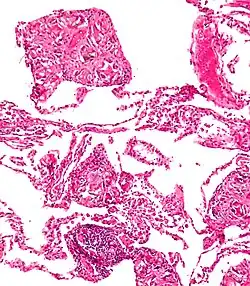

Foreign body giant cell reaction to nylon suture material -

Foreign body granuloma